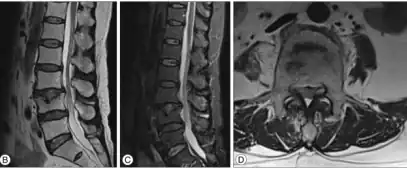

b,c,d) MRI present a minimal Schmorl's node at L4

Schmorl's nodes can be detected with X-rays, although they can be imaged better by CT or MRI. They are considered to be vertical disc herniations through the cartilaginous vertebral body endplates. Schmorl's nodes can sometimes be seen radiographically, however they are more often seen on MRI, even when not visible on plain X-rays. They may or may not be symptomatic, and their etiological significance for back pain is controversial. In a study in Spine by Hamanishi, et al., Schmorl's nodes were observed on MRI in 19% of 400 patients with back pain, and in only 9% of an asymptomatic control group. The authors concluded that Schmorl's nodes are areas of "vertical disc herniation" through areas of weakness in the endplate.[4]